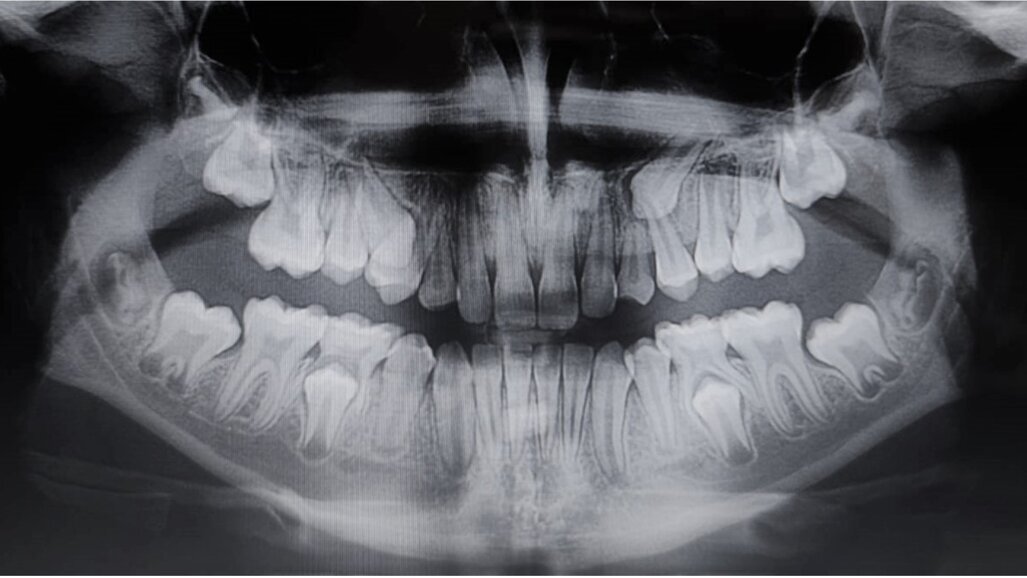

Eziologia La trasposizione dentale sembra avere una eziologia multifattoriale dove un ruolo importante è ricoperto dalle cause genetiche e dalle cause ambientali9. Alcuni Autori avvalorano maggiormente la teoria genetica10, sostenendo che un’alterazione nello sviluppo dentale produca, contestualmente alla trasposizione, varie anomalie dentali, quali ad esempio: agenesie dentali, incisivi laterali conoidi, etc. 2,7,11. Inoltre, l’interessamento bilaterale dello stesso dente, la presenza di trasposizione dentale in pazienti sindromici, come nella sindrome di Down12 o nella displasia cleidocranica13, il riscontro dell’anomalia in gemelli monozigoti14, sono altre evidenze che possono confermare l’eziologia genetica. In Figg. 1a, 1b è riportato un interessante caso di due gemelle eterozigoti che mostrano entrambe trasposizione canino-premolare mascellare e ritenzione canina.

Figg. 1a, 1b - Rx-OPT della paziente 1 (A) e della paziente 2 (B) gemelle di anni nove e mezzo entrambe in trattamento ortodontico intercettivo. Si nota la particolare e contemporanea presenza sia della trasposizione canina-premolare sia della ritenzione canina superiore.